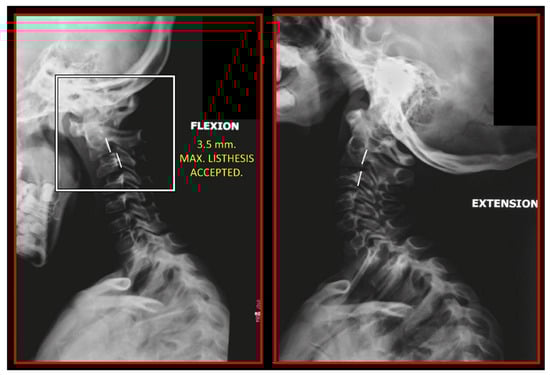

- Rocabado, M.; Gutierrez, R.; Gutierrez, M.F.; Gutierrez, M.J. Case report: Anterior open bite correction treatment by dental treatment and physical therapy through craniocervical mandibular and occlusal stabilization. Cranio 2021, 10, 1–6. [Google Scholar] [CrossRef]